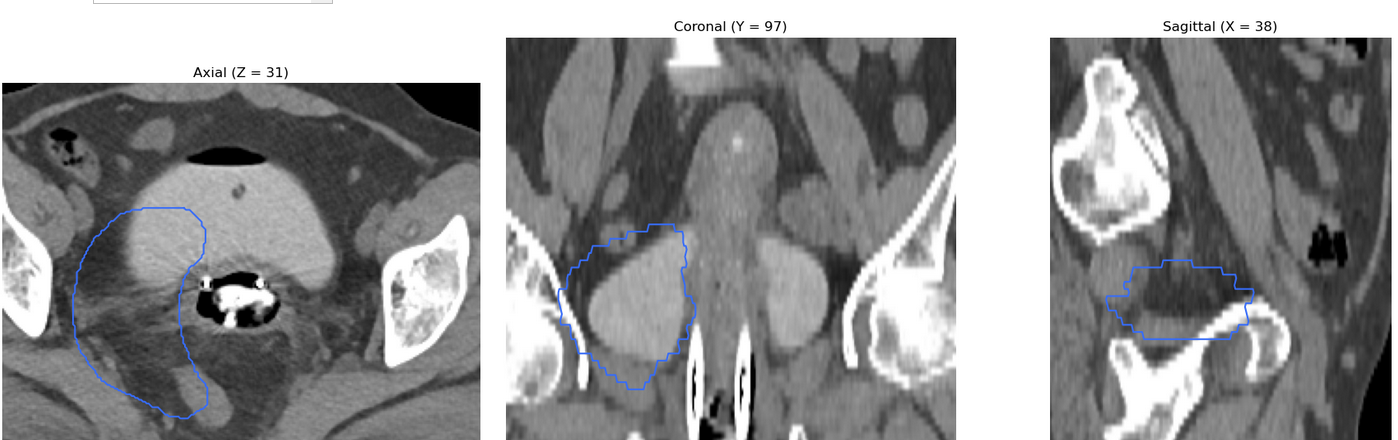

I am working on displaying CT images in the axial, coronal, and sagittal planes, along with dose maps and RTSTRUCT contours. While the CT and dose images are displayed correctly, I am having trouble overlaying the structures (contours) from the RTSTRUCT file on the CT images—the contours do not align properly with the CT, as shown in the attached image.